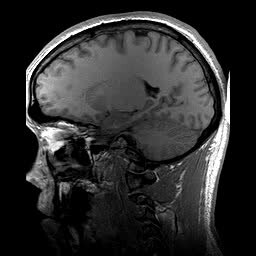

Magnetic Resonance Imaging (MRI)

Magnetic Field Gradient

Magnetic field gradients revolutionized MRI by turning invisible signals into detailed body maps

Medical Imaging

Magnetic resonance imaging transformed diagnostics by revealing soft tissues without harmful radiation

Double Inversion Recovery

Double inversion recovery reveals brain lesions hidden from conventional MRI scans

Magnetic resonance imaging reveals the body's inner workings without harmful radiation exposure